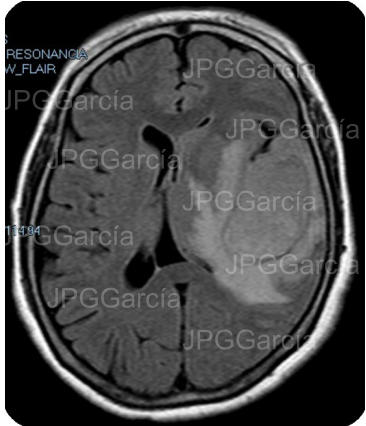

Resonancia magnética de cráneo en secuencias T1 y T2 que muestran una lesión ocupante de espacio de localización fronto temporal izquierda que ejerce efecto de masa aunado a edema perilesional